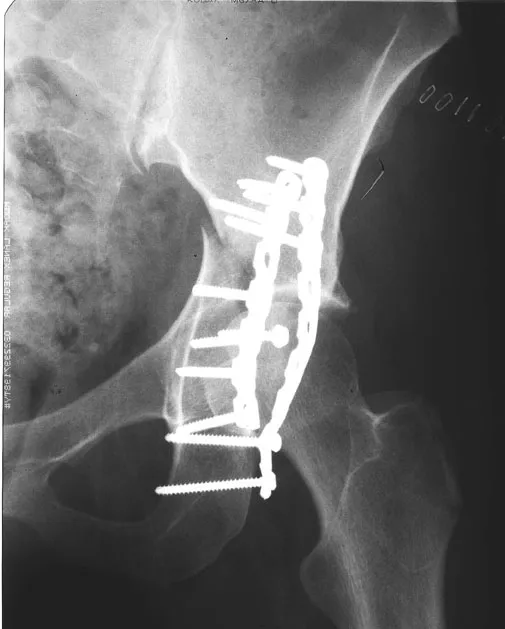

This piece is intended to be a part of a legal exhibition used by the plaintiff's attorney for an injury case. The objectives are to visually communicate the client's injury and the following operative procedure, to help the plaintiff win the case. I was given the accident report and the medical documents to create the visuals for this case. Relatively graphic details were shown in the surgical illustration in order to emphasize the gruesome nature of the client's injuries.